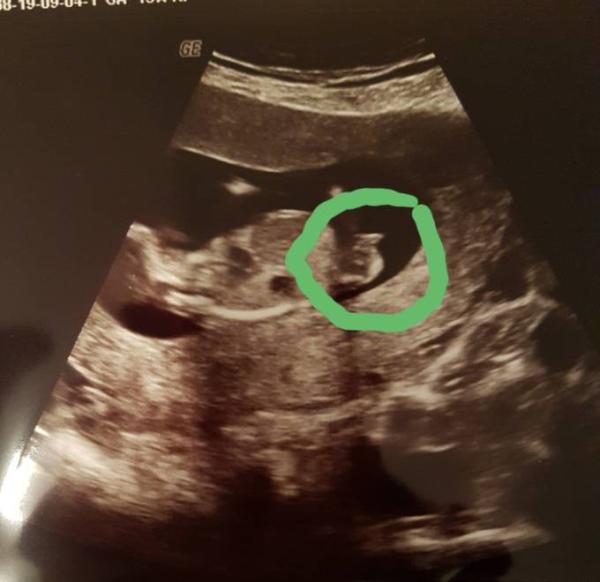

Hi zusammen Meine Blutwerte sind da und es liegt keine Trisomie vor und Team rosa wurde bestätigt. Siehe Bild Ich bin so froh und erleichtert. Jetzt muss die Zeit bis feb. März nur schnell rum gehen. Bei 4 FG sieht man überall Gespenster. Lg

Bild zu Outing Mädchen - Forum für März - Mamis